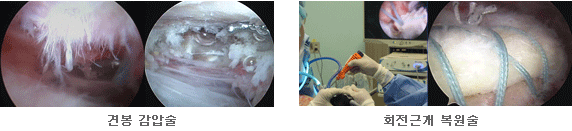

경도의 충돌증후군이 있으면 휴식과 투약 그리고 물리치료를 통해 염증을 완화시키고 위축된 근육의 근력을 회복시킬 수 있다. 통증을 유발할 수 있는 활동은 통증이 없을 때 서서히 재개해야 한다. 필요 시 주사치료로써 종창과 염증을 줄일 수 있으나, 약제와 주사횟수 및 시술 방법 등에 유의하여야 한다. 6개월 이상의 보존적 치료에도 증상의 호전이 없을 경우 관절경을 이용한 수술적 치료를 시행할 수 있다. 회전근 개의 완전파열이 있으면 수술적 치료로 건을 봉합하는 것을 일차적으로 고려할 수 있다. 수술방법의 선택은 증상의 정도, 환자의 건강상태, 견관절의 활동량 등에 의해 결정된다. 젊고 활동량이 많은 사람의 경우 대부분 건의 봉합이 필요하나, 활동양이 적은 노인의 경우 보존적 치료로도 증상의 완화가 되는 경우가 많으며, 필요 시 부분적 봉합만으로도 좋은 결과를 보기도 한다